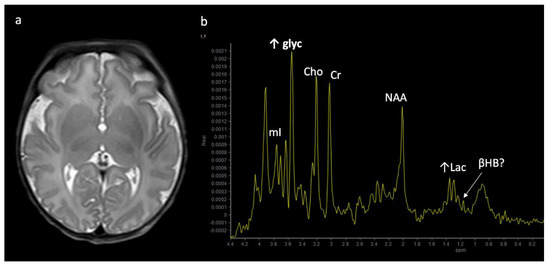

Metabolite ratios change based on age, with the most dramatic changes in the first three months of life. Familiarity with normal age-related metabolite ratios is crucial for accurate interpretation [4,5,15]. An example short TE single-voxel (SVS) MRS performed at 3T is shown in Figure 1. The major metabolites include N-acetylaspartate (NAA at 2.0 ppm, neuronal metabolite and biomarker for viable neurons or assessment of parenchymal damage); creatine (Cr at 3.0 and 3.9 ppm, includes free creatine and phosphocreatine, marker of energetic reserve); choline (Cho at 3.2 ppm, marker of cellular proliferation from increased membrane turnover and/or inflammation); myo-inositol (mI at 3.5 ppm, glial metabolite, osmolyte, and marker of gliosis and/or neuroinflammation); lactate (Lac at 1.3 ppm, reflects anaerobic glycolysis); lipid/macromolecules (LipMM at 0.9 and 1.3 ppm from -CH3 and -CH2 groups, respectively); and glutamate (Glu at 2–2.5 ppm, excitatory neurotransmitter) and glutamine (Gln at 2–2.5 and 3.6–3.9 ppm, osmolyte and hyperammonia detoxifier) [4,5,15,16].

Figure 1.

Example of a normal 3T 1H SVS (basal ganglia VOI) in a 3-month-old child using PRESS TE = 35 ms. Metabolic ratios change with age, with the greatest differences in the first 3 months of life. All spectra in this paper are obtained using similar parameters although voxel location is variable. Abbreviations: Cr, creatine + phosphocreatine; Cho, choline; Glu, glutamate; Gln, glutamine; Glx, glutamine + glutamate; mI, myo-inositol; MM, macromolecules; NAA, N-acetylaspartate; SVS, single voxel spectroscopy; VOI, voxel of interest.